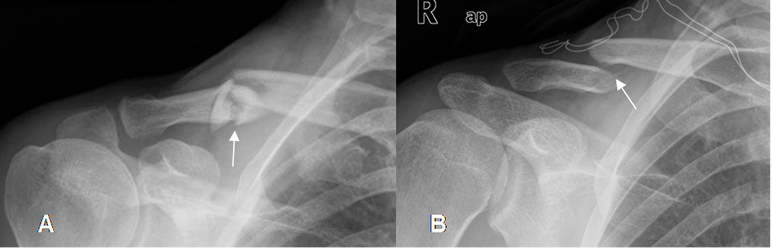

Fig 37. Fractura de clavícula.

A: Rx AP. Fractura conminuta del tercio medio, con leve angulación superior.

B: Rx AP. Fractura cabalgada del tercio medio, con desplazamiento superior del extremo proximal y diastasis de la articulación acromioclavicular.